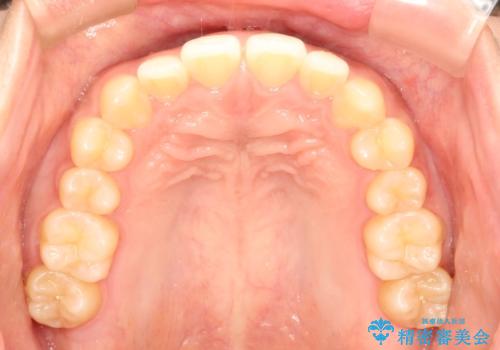

前歯の隙間を閉じたい。インビザラインによる治療

- 前歯の隙間を閉じたいと矯正カウンセリングに来られた患者様です。

マウスピース矯正(インビザライン)を行い短期間で治療が完了しました。